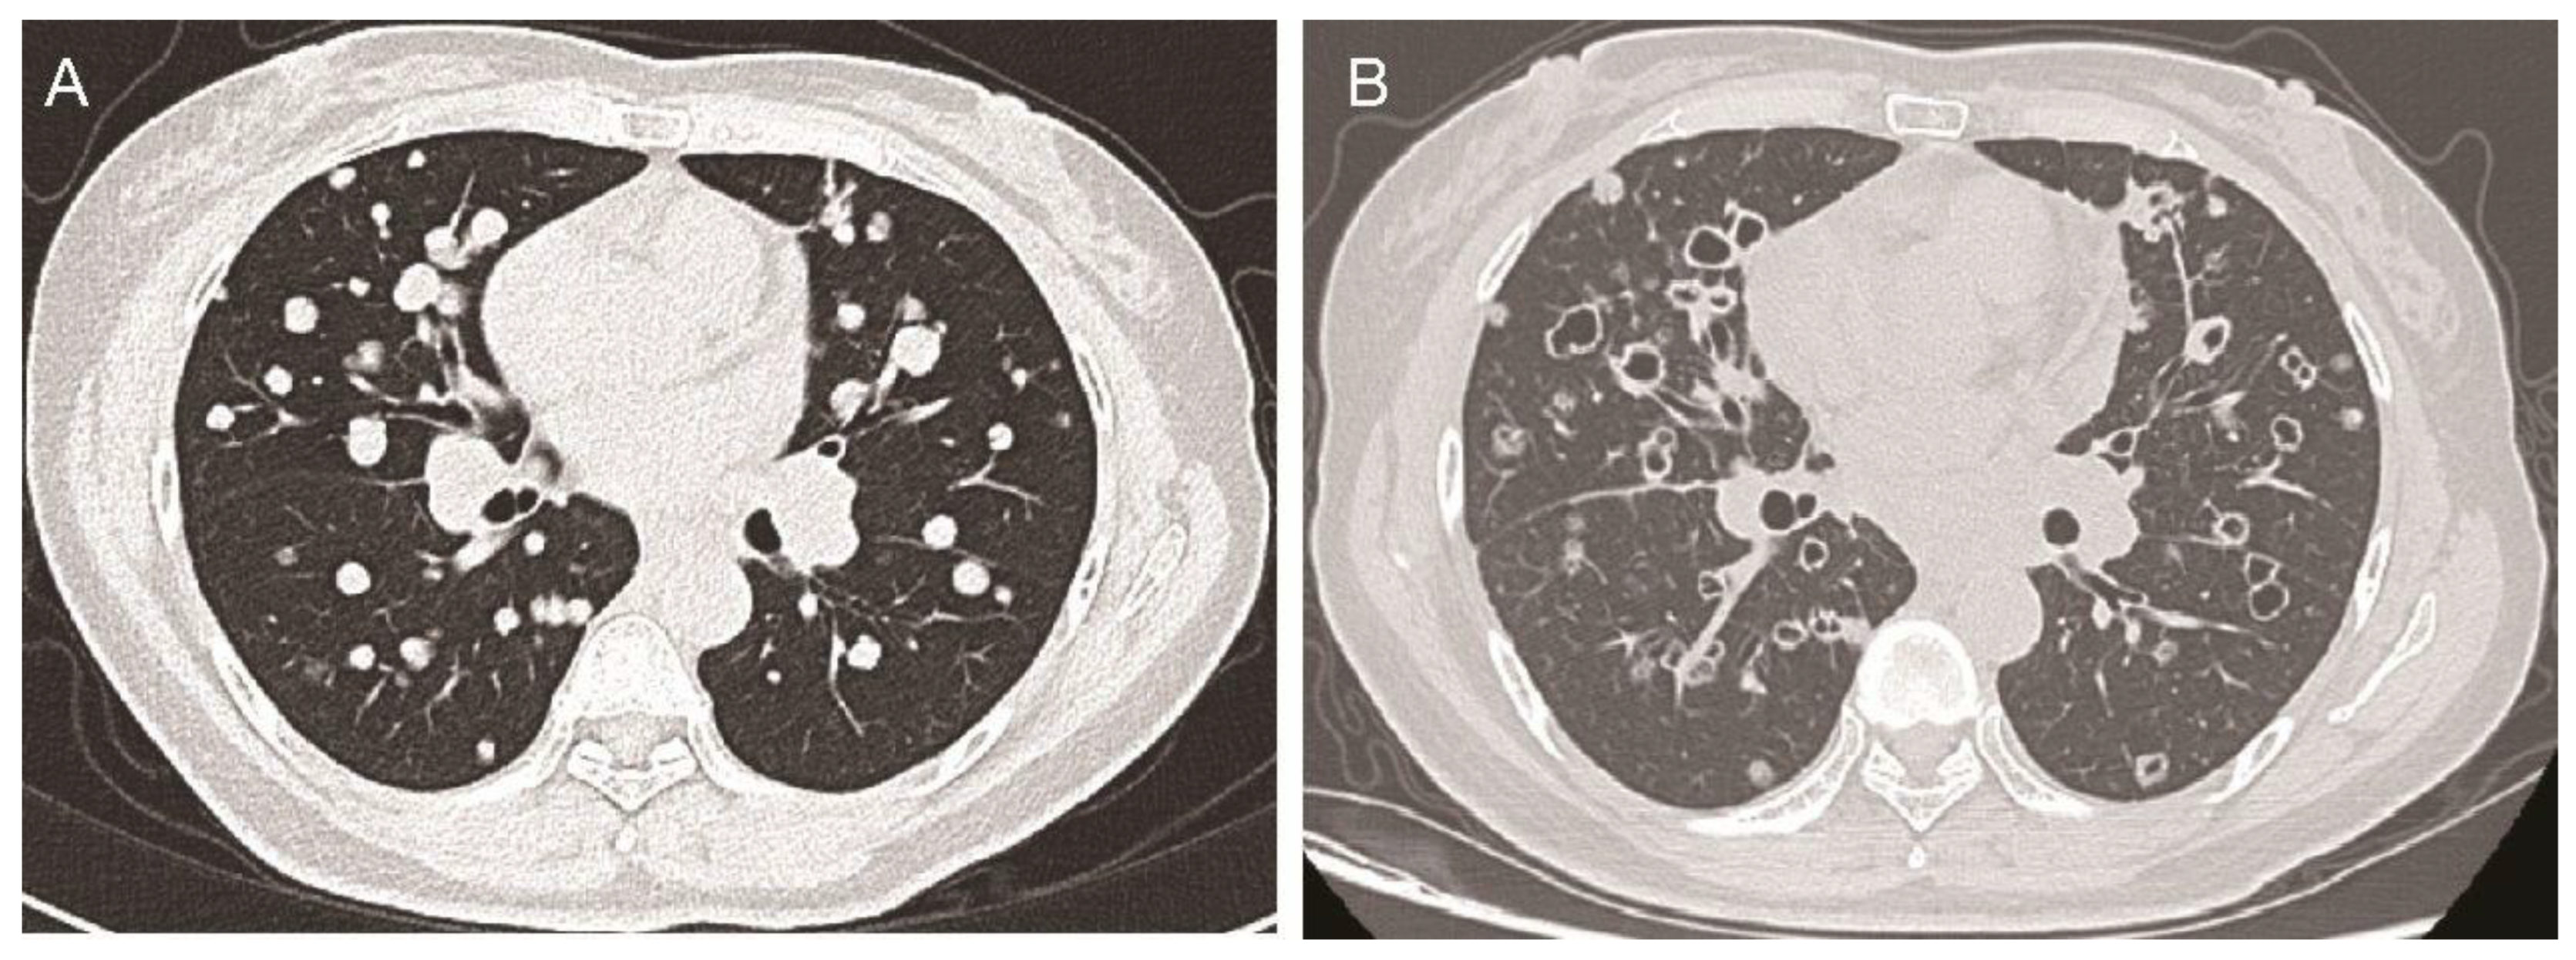

Subsequent administration of standard first-line and second-line systemic chemotherapies also failed to arrest tumor progression. Consequently, the patient received a combination therapy comprising the orally taken third-generation EGFR TKI aumolertinib at a dose of 110 mg daily and the small-molecule angiogenesis inhibitor anlotinib [1] at a dose schedule of 12 mg daily, 2 weeks on/1 week off. Baseline chest computed tomography (CT) scans revealed multiple solid metastatic nodules in the bilateral lungs (Figure 1A). Notably, after 6 months of this combination therapy, the chest CT scans demonstrated near-complete cavitation of the lung nodules, manifesting as “bullet holes” (Figure 1B). Along with the remarkable imaging feature, which was attributed to the anti-angiogenic effects of anlotinib, the CEA levels also dropped from 650 ng/mL to 430.2 ng/mL, and the patient reported a partial relief of shortness of breath.

Figure 1. The chest CT scans of the patient before and after anlotinib treatment. (A): Axial chest CT scan showing multiple solid metastatic nodules in bilateral lungs at the baseline before anlotinib treatment. (B) After 6 months of anlotinib treatment, the axial chest CT scan shows that almost all nodules with tumor cavity looked like holes shot by bullets.